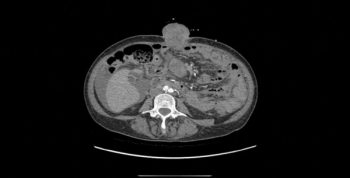

We present the case of a 51-year-old woman with metastatic International FIGO stage IIIC ovarian cancer who had delayed her therapy after initial laparoscopy due to COVID-19 infection and presented with an extreme case of surgical port metastasis.